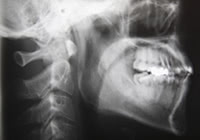

しかし矯正歯科医は、どういった情報をもとにその人の歯並びや噛み合わせの特徴を捉えているのか、みなさんは考えたことがありますか。矯正歯科医が矯正治療をする前に必ず行う検査とされているのが『セファロ検査』というものです。この検査を行うことで矯正歯科医は患者の状態を詳しく分析し、それをもとに正確な矯正治療を行っているとされています。